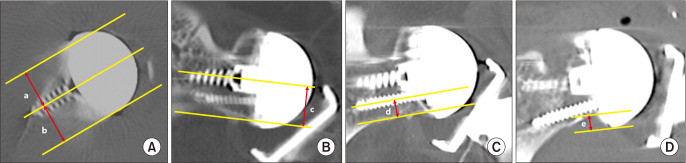

Methods: This prospective study enrolled 120 patients who underwent RSA for a symptomatic irreparable massive rotator cuff tear, cuff tear arthropathy, or primary osteoarthritis with a full-thickness rotator cuff tear. Patients were randomly allocated 2:1 to receive an Asian-type RSA implant (group I) or conventional RSA implant (group II). All patients underwent plain radiography to evaluate acromiohumeral distance, acromion-deltoid tuberosity distance, lateral humeral offset, and center of rotation distance. Postoperative 1-year computed tomography (CT) scans were obtained for all patients to evaluate the position of peg screws and baseplates and the presence of scapular notching. Clinical outcomes were evaluated using American Shoulder Elbow Surgeons (ASES) score, Constant score, and active range of motion.

Results: Finally, 112 patients (80 in group I and 32 in group II) were included in this study. The mean patient age was 74.0 ± 5.5 years, and the mean patient height was 154.6 ± 8.1 cm. At the last visit, clinical scores and active range of motion significantly improved in both groups; however, the improvements did not differ significantly between the 2 groups. On the postoperative 1-year CT scan, the glenoid baseplate was more anteriorly placed in group II than in group I. The supero-inferior position of the glenoid baseplate did not significantly differ between the 2 groups. Other radiological parameters obtained through plain radiography showed no significant differences between the 2 groups. No differences were found in scapular notching (p = 0.999) and acromial stress fracture (p = 0.872) between the 2 groups.